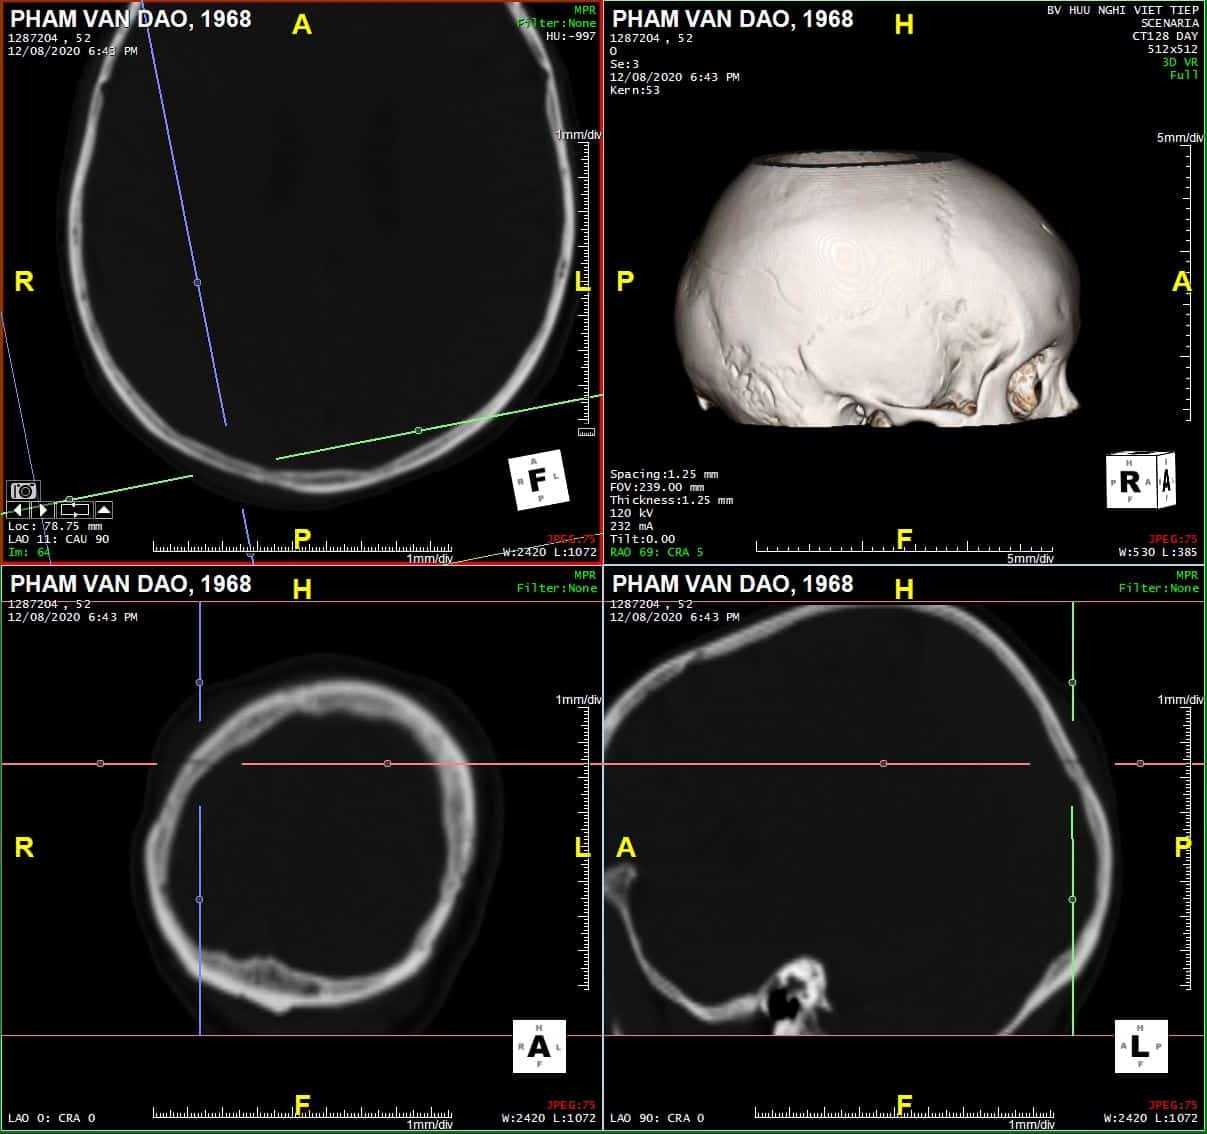

Coronal

Sagittal

# Tụ máu ngoài màng cứng vùng chẩm phải / Vỡ xương chẩm phải: đường vỡ thẳng (Linear fracture) không thấy rõ trên hướng cắt Axial => quan sát rõ trên hướng cắt Coronal và Sagittal.